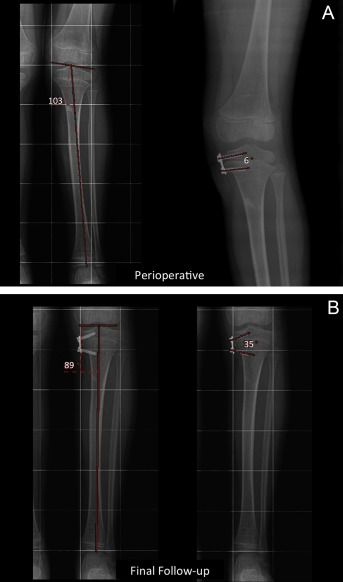

An application of the formulas to estimate d-JOA from d-ISA is depicted in Fig. 3 A and B. This is a case of Cozen phenomenon. The values are as follows: MPTA perioperative 103°, MPTA final follow-up 89°. ISA perioperative 6° and ISA final follow-up is 35°. By taking an AP knee X-ray only, one would be able to estimate the difference in the joint orientation angle (MPTA). For that purpose the following formula for tibias should be chosen (ΔJOA = 1.385 + 0.457 × ΔISA).

Fig. 3

Fig. 3.

A 5-year-old female patient who developed Cozen phenomenon after a proximal metaphyseal fracture. Her left medial proximal tibial angle (MPTA) was 103°, and the ISA was 6° when the eight plate was first applied (A - Perioperative). In 16 months the MPTA changed to 89° and the ISA changed to 35° (B – Final Follow-up).

d-ISA in this case is 35–6 = 29°.

14.6° is the amount that is estimated by this formula using the difference between the ISAs before and after correction at the time of the X-ray.

(95% Confidence interval 0.615–0.854)

103–14.6 = 88.4° is the estimate for the current MPTA with the help of the formula and the difference of ISAs. The real MPTA was 89°.

Thus, this example shows that by knowing the change in the ISA, which was 29° in this case, it might be possible to predict the amount of change in joint orientation angle that is around 14 degrees of change in MPTA in this case.